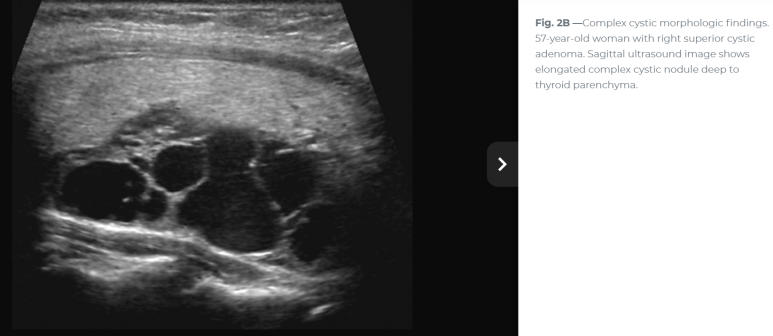

2개가 아니라 연결되어 있으며 격벽처럼 관찰되는데... 1.75 cm

연속 사진으로 내측의 경계가 불규칙하거나 격벽 변화가 있는 모습

확대하면 두꺼운 벽처럼 보이는 부분도 있다. 거꾸로 아래쪽 어두운 곳은 낭성 변화

Imaging included parathyroid ultrasonography, which revealed a cystic appearing mass with septations and mild irregularity (격벽과 불규칙한 내부 경계를 보이는 낭성 종괴)

이번 사례와 같은 위치에 비슷한 모습